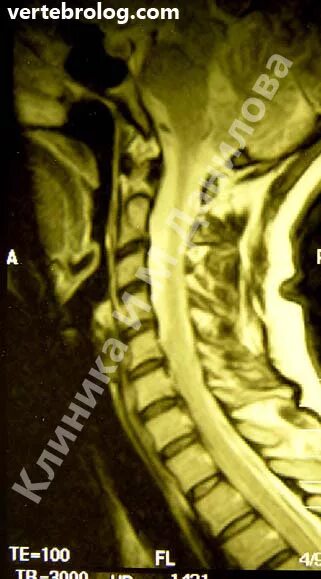

Протрузия дисков с5 с7 шейного отдела